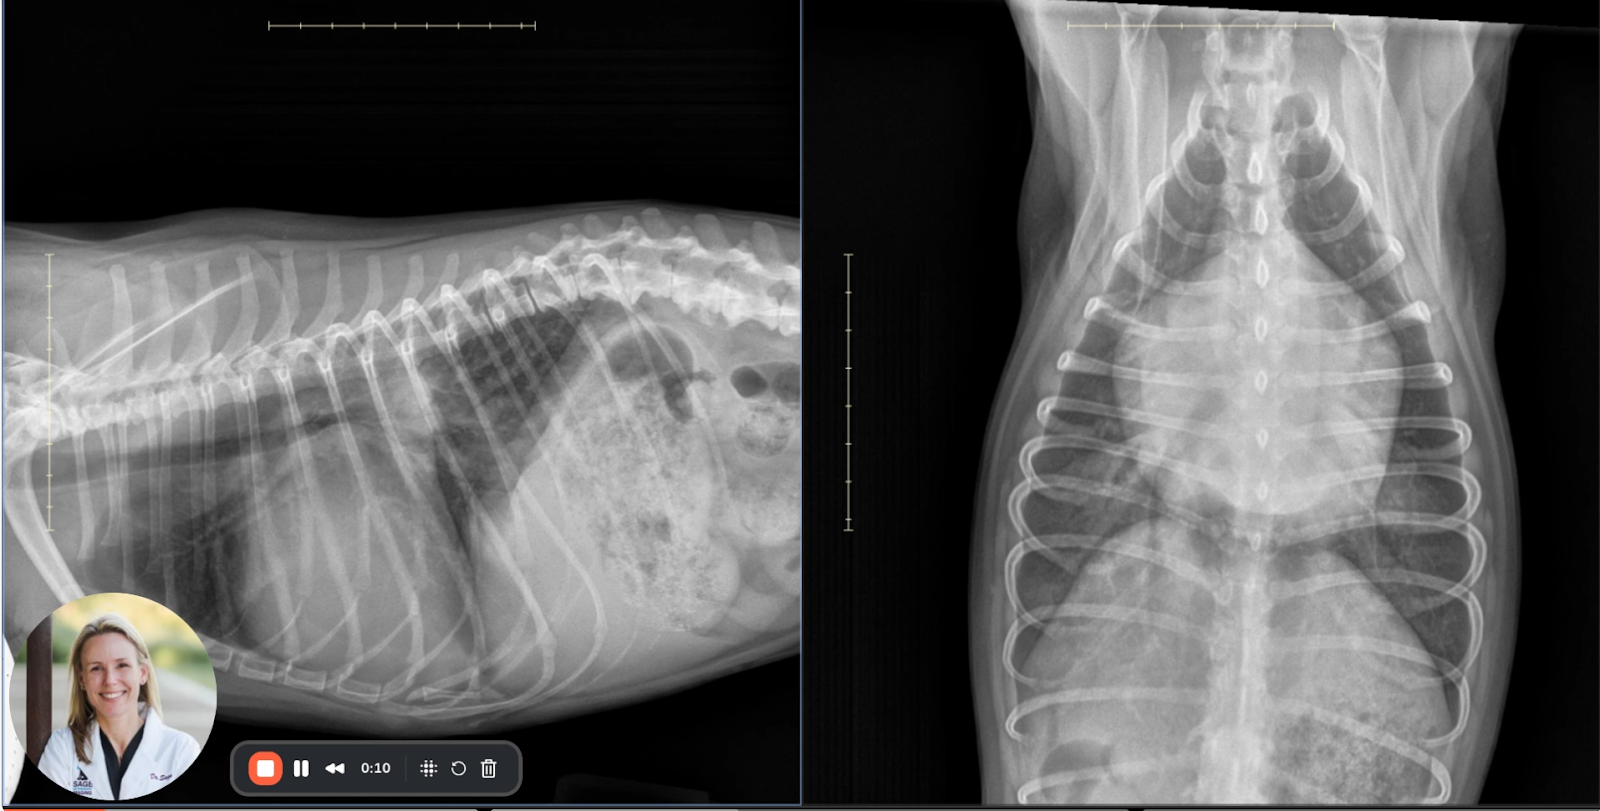

Side-by-side radiographic comparison of VD and lateral projections in a CHF case.

Image 3: Composite Overview

This comparison reaffirms the findings described above and offers a helpful orientation of the orthogonal projections. The right lateral and VD images together confirm both left atrial and ventricular enlargement, vascular congestion, and pulmonary edema.